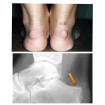

– Так, лечение деформации стопы

(включая плоскостопие и вальгусную деформацию

первого пальца) помогает исправить походку

и предотвратить дальнейшие осложнения.